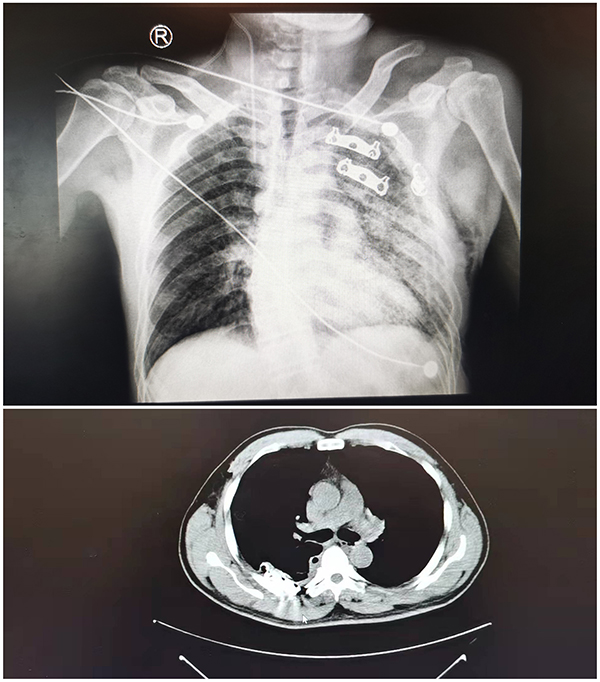

日前,47歲的楊大伯不慎從高處墜落,導(dǎo)致全身多處擦傷并短暫昏迷,被送到我院急診科搶救。醫(yī)生經(jīng)過胸部(胸廓肋骨)平掃+三維骨成像(64排CT)檢查發(fā)現(xiàn)患者全身多處嚴(yán)重骨折,分別為左側(cè)第1-9肋、右側(cè)第5-8肋多發(fā)骨折;兩側(cè)氣胸,左肺壓縮約30%,右肺壓縮約5%;左肺各葉及右肺中葉挫裂傷;左側(cè)胸腔少量積液/積血;左側(cè)胸壁軟組織積氣。情況十分危急,如果不及時(shí)實(shí)施手術(shù)治療,將會(huì)嚴(yán)重影響患者日后的生活質(zhì)量。

術(shù)前影像

楊大伯的手術(shù)過程很順利,通過胸腔鏡微創(chuàng)手術(shù)治療,楊大伯肋骨骨折、1500ml血性胸腔積液、肺部1cm裂口等問題得到了同步處理。此外,由于手術(shù)創(chuàng)面只有短短的4厘米,使患者術(shù)后疼痛極大減輕,可以較早地下床活動(dòng)。經(jīng)復(fù)查胸片及胸部CT提示患者肋骨斷段固定、愈合良好,對(duì)比傳統(tǒng)手術(shù)方式大大縮短康復(fù)時(shí)間,可以使患者更早地恢復(fù)正常生活。

術(shù)后影像